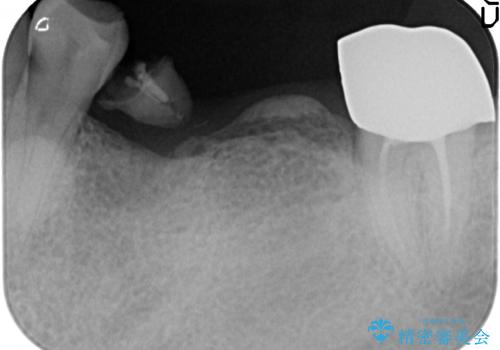

欠損部位である左下5、6番目にインプラントを埋入し、オールセラミッククラウンによる補綴を行いました。

左下7番目は再根管治療を行い、オールセラミッククラウンによる補綴を行いました。

- オールセラミッククラウン…¥100,000×3、仮歯…¥10,000×3、インプラント(ストローマン)…¥200,000×2、カスタムアバット…¥100,000×2、ファイバーコア…¥20,000、根管治療費別途費用は治療当時の料金となります